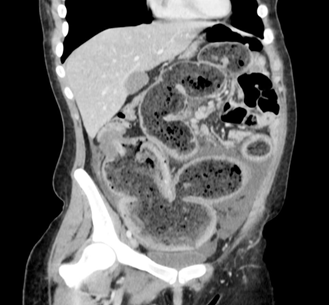

of 124 k/ul. An abdominal computed tomography (ct) scan

with oral and intravenous contrast demonstrated a dilated obstructed large

bowel with a suspicious concentric mass at the hepatic flexure (figure 2).

Figure

2: abdominal computed tomography (ct)

scan with oral and intravenous contrast demonstrated a dilated obstructed large

bowel with a suspicious concentric mass at the hepatic flexure